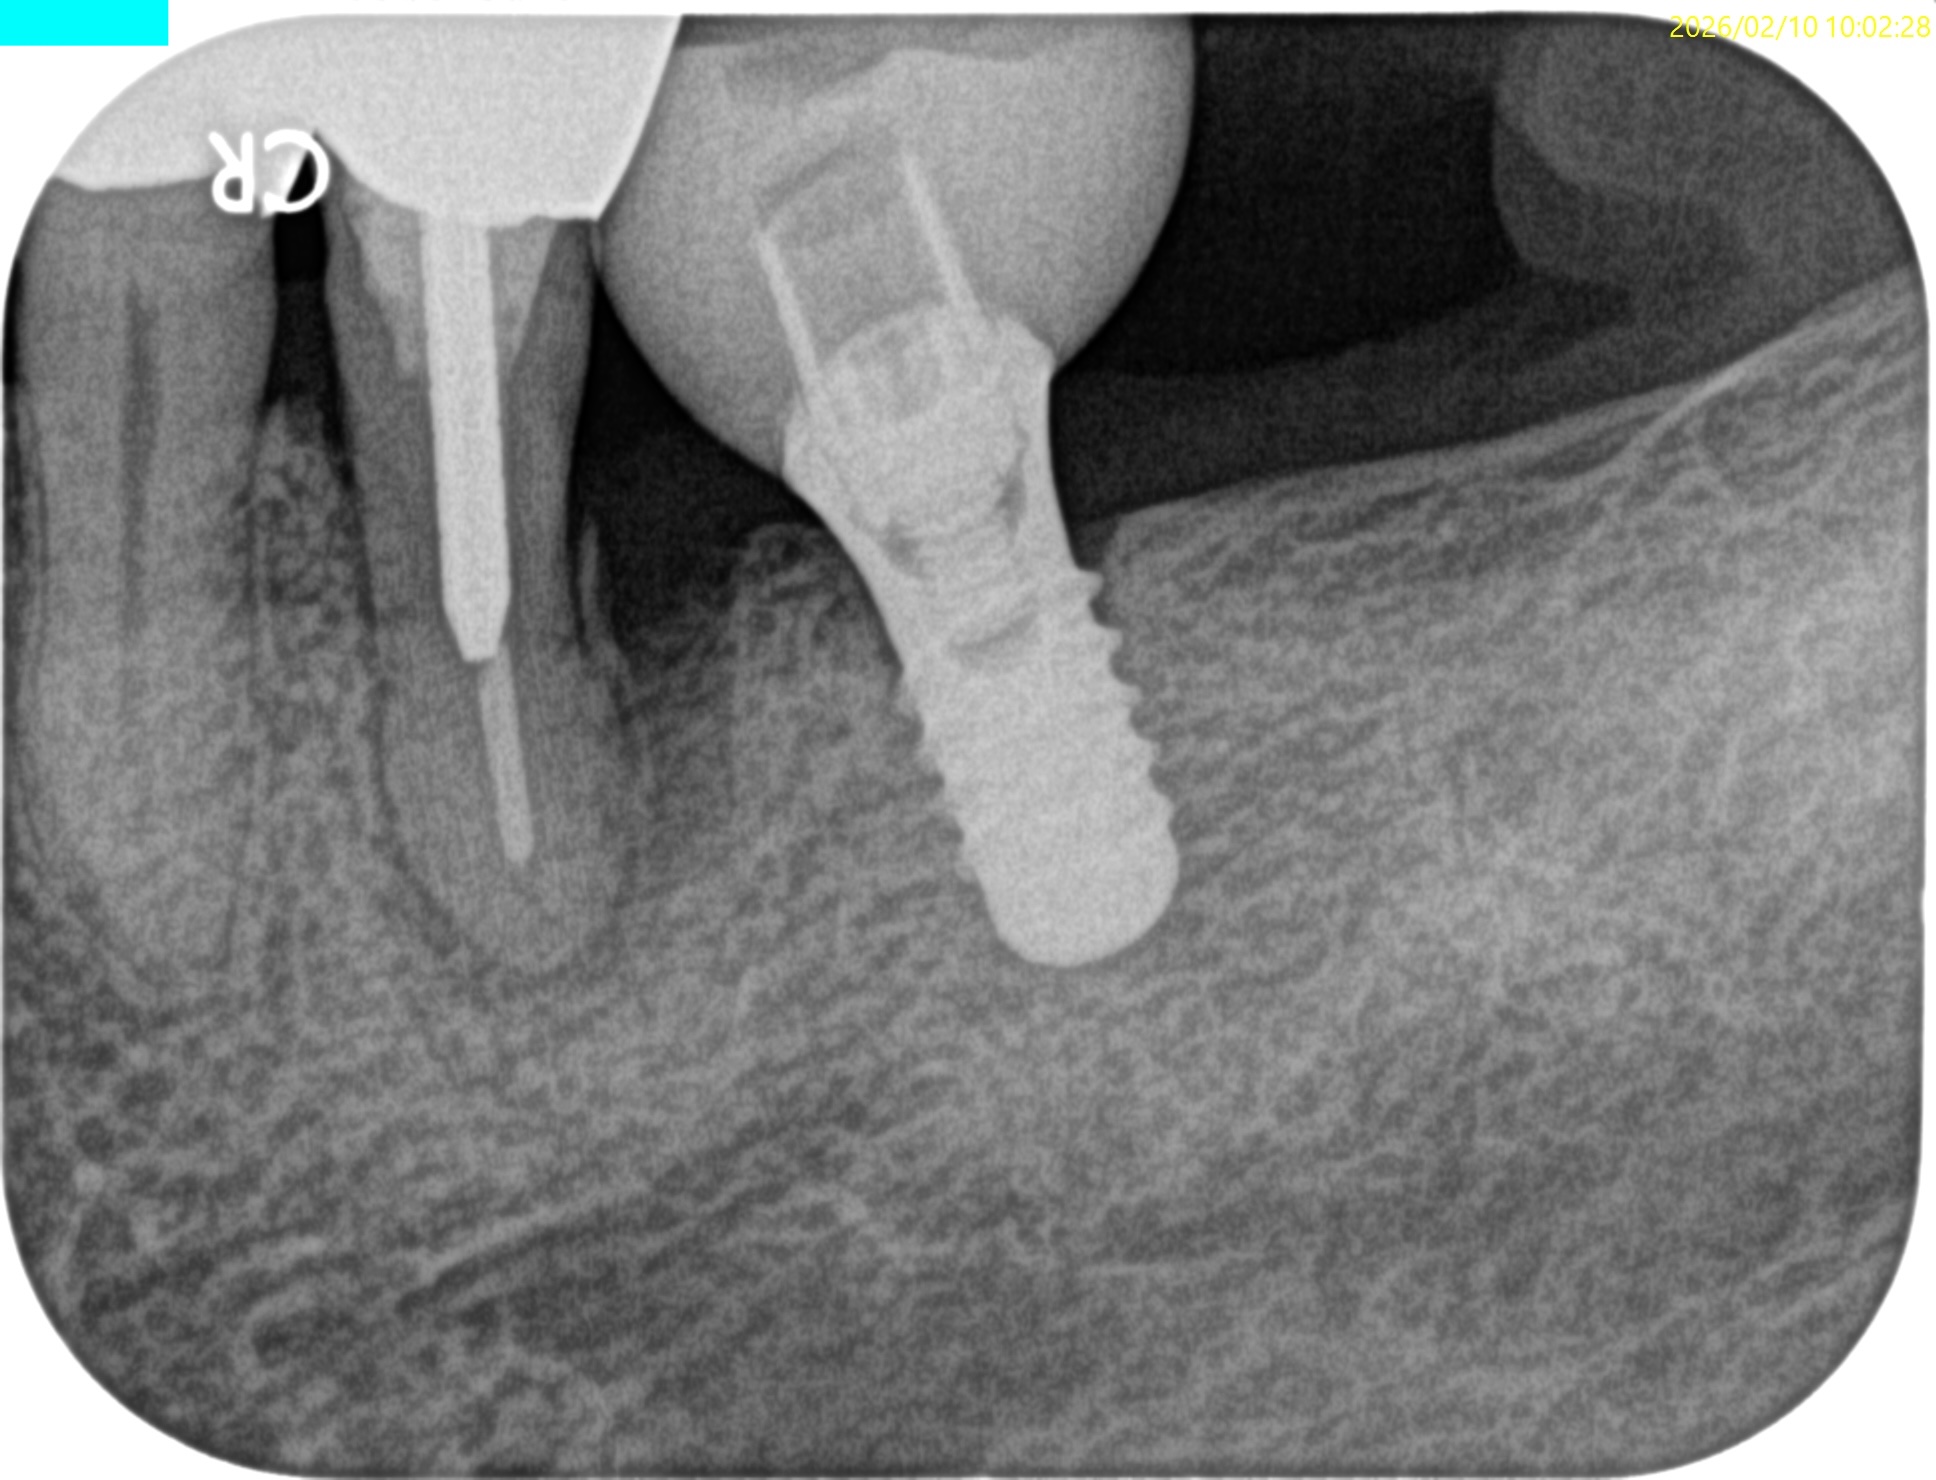

Pre-op Endo test(2026.2.10)

#20は長いピンが装着されており除去に著しく長い時間がかかることが予想される。

スクリューピンの除去には相当時間がかかるとわかる。

つまり、この作業にはかなりの時間を要しそうだ、と言うことが術前に知ることができる。